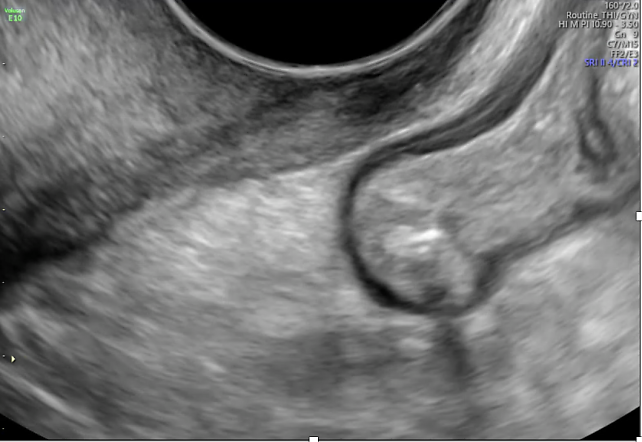

5

Well-circumscribed adenomyoma in a 27-year-old patient, presenting as a heterogeneous, hypoechoic intramyometrial lesion.